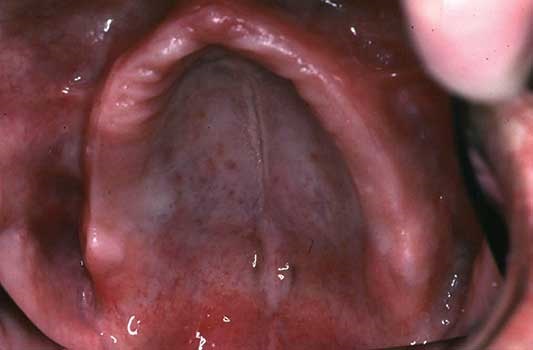

For predictability and success with complete dentures, it’s essential to treat patients who have stable (not changing) stomatognathic systems; this includes stable (noninflamed) denture-supporting tissues and temporomandibular joints (TMJs). If final impressions are made of unstable inflamed, swollen tissues (Fig. 1a), the denture will not fit well to the healed, unswollen tissues (Fig. 1b). Other conditions that can lead to unpredictability include the absence of retromolar pads, hypertrophied maxillary tuberosities, large tori or exostoses (Fig. 2), salivary hypofunction and mobile (displaceable) alveolar ridge soft tissues (Fig. 3). Also, any pathologic areas detected during the oral cancer screening, which should be part of the oral examination, should be addressed before beginning denture fabrication.

Fig. 3